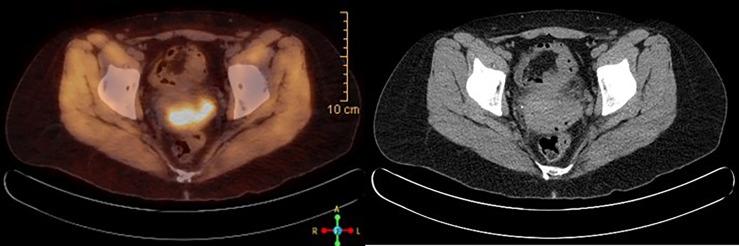

The incidence of cervical cancer has decreased in recent years due to widespread vaccination and routine screenings. It can be treated successfully, and the prognosis is also excellent if detected early. However, the 5-year survival rate for patients with stage IV cervical cancer is only 17% even with aggressive systemic chemotherapy. With the Food and Drug Administration (FDA)'s approval of immunotherapy, the prognosis has improved. We present a patient with stage IV cervical cancer who could not tolerate platinum-based chemotherapy and bevacizumab, so she was started on an immune checkpoint inhibitor, as her tumor was 100% programmed cell death ligand-1 (PD-L1) positive. She survived more than 2 years since the diagnosis of stage IV cervical cancer without any significant side effects. Based on our patient's response, the use of immune checkpoint inhibitors as a single agent needs further research and probably can be considered in patients with stage 4 cervical cancer who cannot tolerate standard chemotherapy.